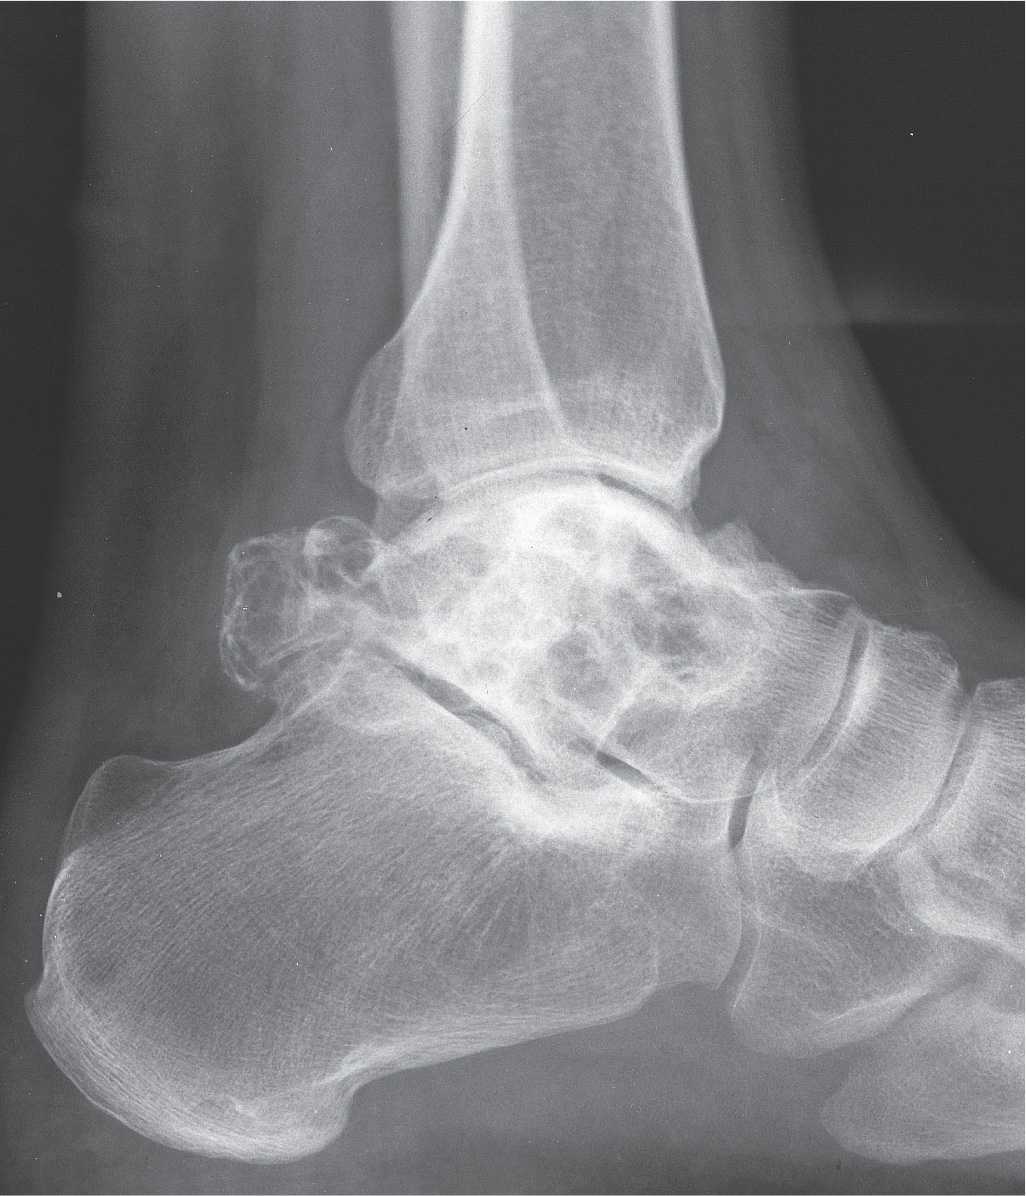

From www.bonetumor.org

A lesion in the talus of an 88 year old woman with 2 previous tumors Talus Bone Tumor Results revealed 75 cases of talar lesions. Radiologists as well as orthopaedic surgeons need to be. Osseous neoplasms of the foot are uncommon, accounting for only 3.3% of all primary bone tumors. Osseous neoplasms of the foot are uncommon, accounting for only 3.3% of all primary bone tumors. Giant cell tumor is a benign primary bone neoplasm which most often. Talus Bone Tumor.